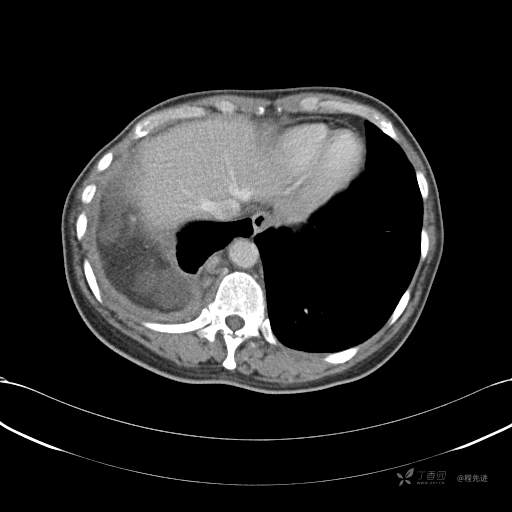

患者性别:女

患者年龄:51岁

简要病史:胸闷半年